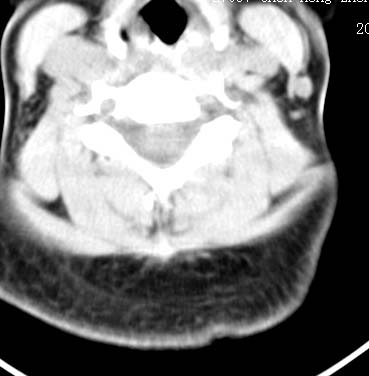

以下是引用sos.la在2008-6-24 5:29:00的发言:[br]可疑项部皮下脂肪肉瘤.穿刺活检.

以下是引用pujunzhi在2008-6-24 7:29:00的发言:[br]后颈部脂肪瘤

以下是引用随光逐影在2008-6-24 7:46:00的发言:[br]考虑项部皮下脂肪瘤或脂肪沉积。